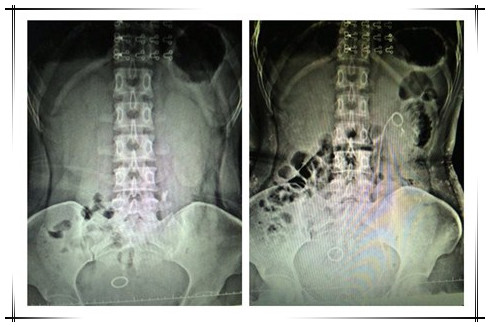

近期,我院普外科应用新近购置的钬激光设备成功为4例输尿管结石患者施行了输尿管镜下钬激光碎石取石术,均获得临床很好的效果。

随着医疗科学技术的飞速发展,近年来,钬激光以安全、微创、高效、低耗、经济、省时且副作用极低等显著优势,而成为治疗尿路结石的“新式武器”。我院成功应用钬激光技术,它将造福于广大泌尿外科(如膀胱肿瘤、输尿管息肉、尿道狭窄等疾病)的患者,尤其是尿路结石的患者。